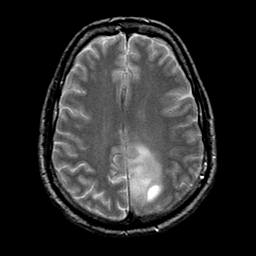

glioma overlay -- Slice #19

[Home][Help][Clinical] Slice 19